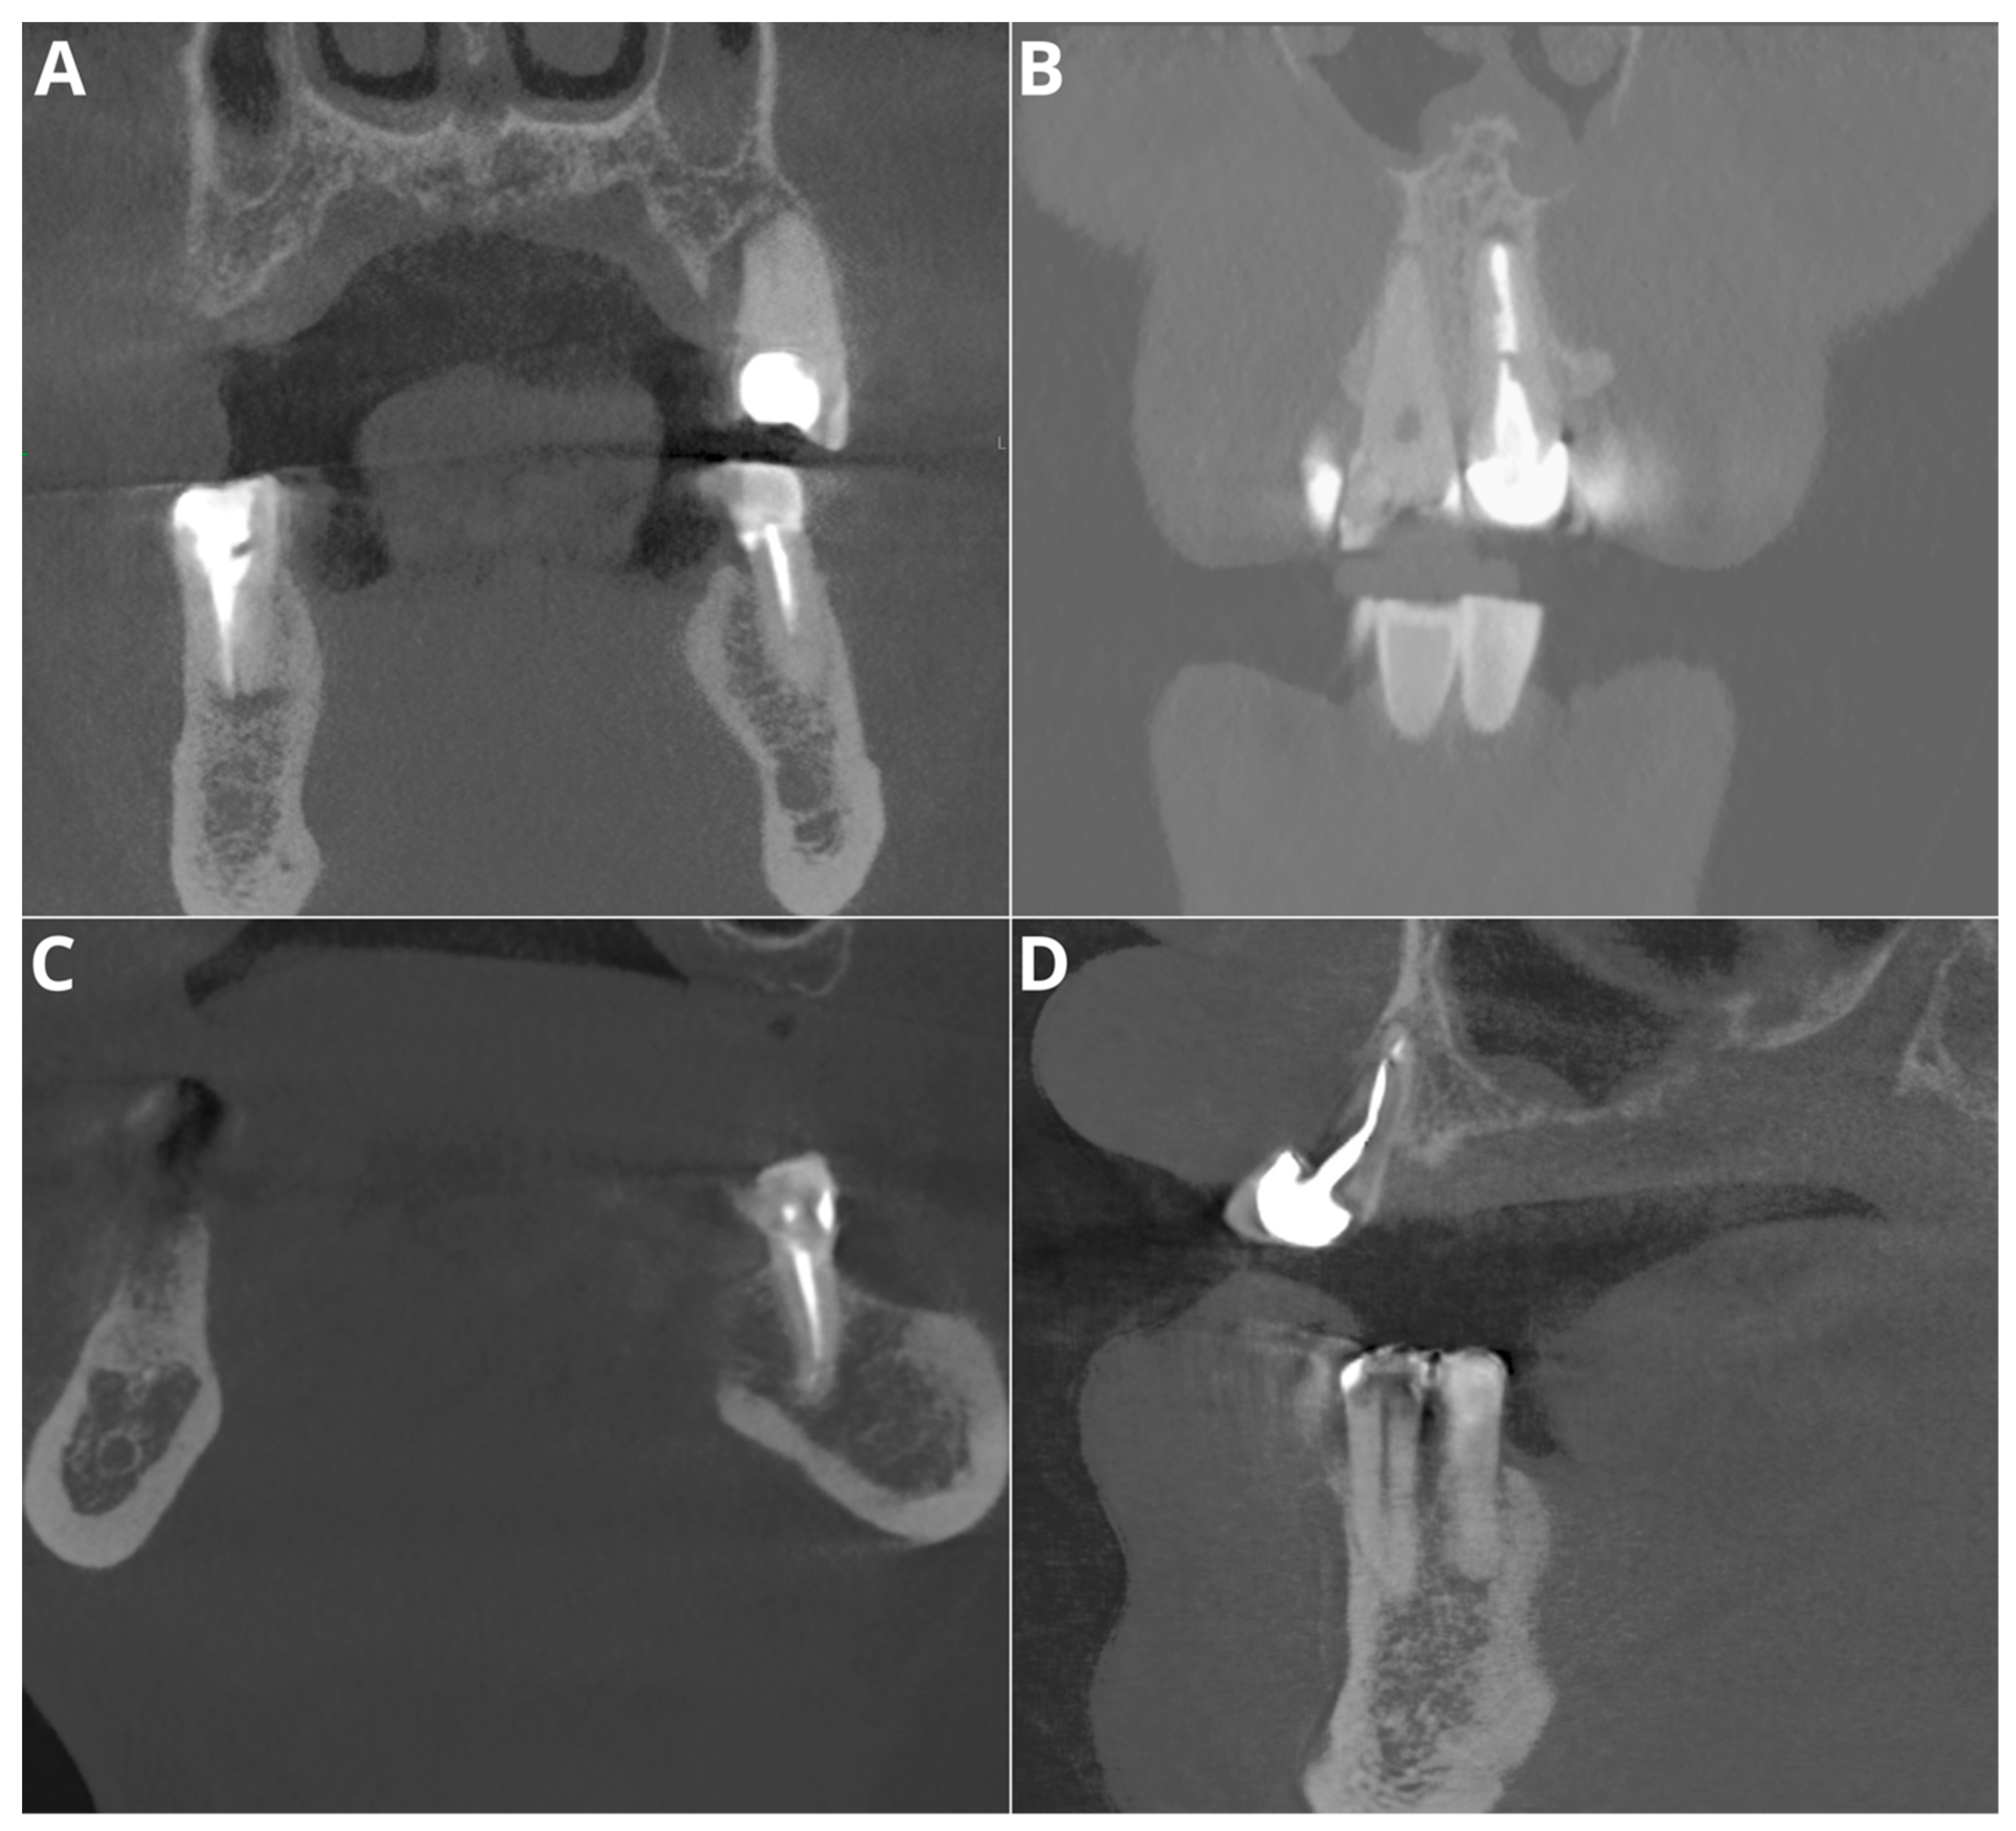

The performance for adequate density was notably high, with an accuracy of 95.5%, a precision of 97.2%, a recall of 97.2%, and an F1 score of 97.2%. Considering that this parameter relies on the subjective evaluation of the readers, we assume that the tested AI program exhibited perfect agreement with the readers’ assessments. Diagnosis revealed overfilling with high accuracy (95.5%), precision (86.7%), recall (100%), and F1 score (92.9%) on the CBCT images. An evaluation of the misdiagnoses revealed that all cases were very subtle (Figure 3). In contrast, Orhan et al. [26] reported a sensitivity of 66.7% for Diagnocat’s overfilling detection on panoramic images. These differences may stem both from the program’s algorithms’ improvements over time and from the different imaging modalities. Moreover, Diagnocat showed exceptional diagnostic accuracy in short-term assessments, with close to 100% accuracy. Figure 4 presents two of the false-negative diagnoses. The detection of voids by the AI program achieved lower performance than other parameters in our study, with 88.6% accuracy, 88.9% precision, 66.7% recall, and 76.2% F1 score. However, Orhan et al. reported a much lower sensitivity of 23.3% for void detection on panoramic images [26]. This discrepancy could be attributed to the 3D imaging provided by CBCT compared to the 2D panoramic images used in Orhan’s study. Our study revealed high accuracy and precision for diagnosing short fillings (95.5% and 100%, respectively), along with a recall of 86.7% and an F1 score of 92.9%. However, Orhan et al. reported a lower sensitivity of 70% [26].

Figure 4. Two of the false negative short-filling diagnoses. (A)—tooth 12, filling 3.5 mm from the apex; (B)—tooth 47, filling 2.8 mm from the apex.